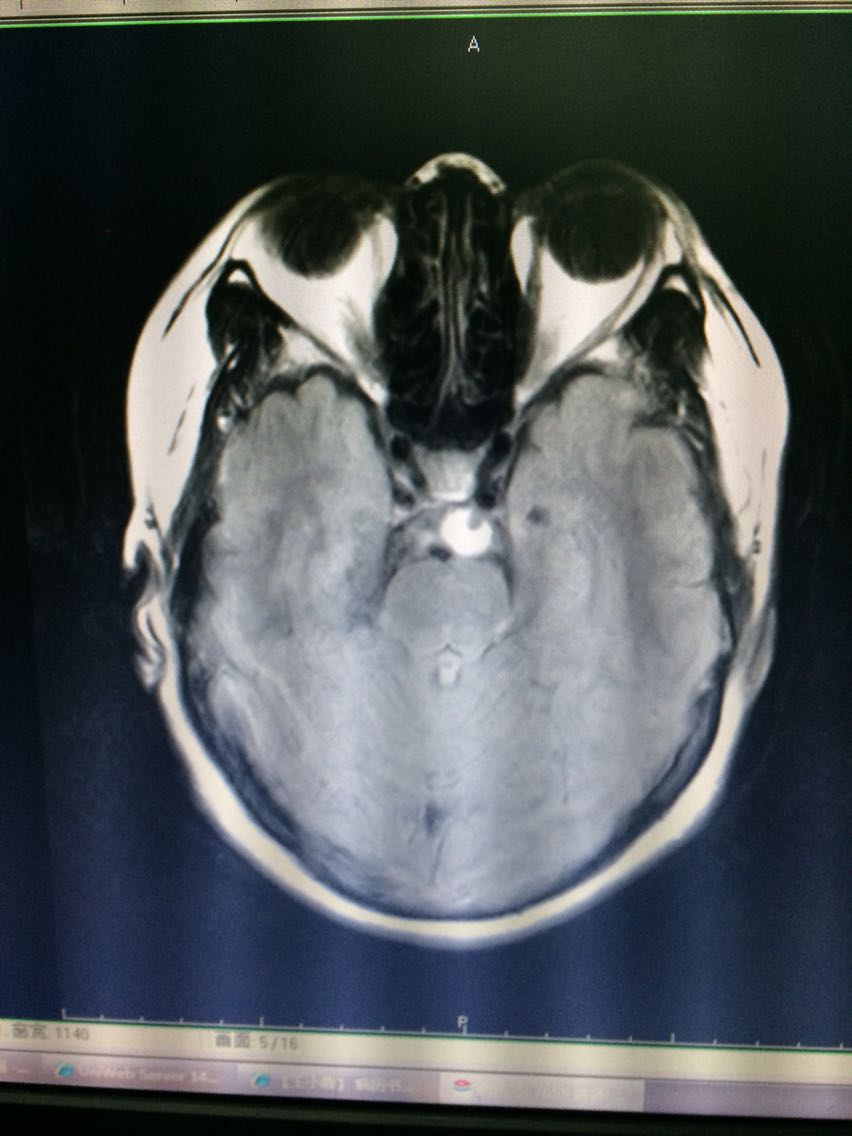

帮忙看看这张片子,在t1,t2上看不见的东西

神经瘤

看看这MRI,奇怪啊,快来帮忙看看?